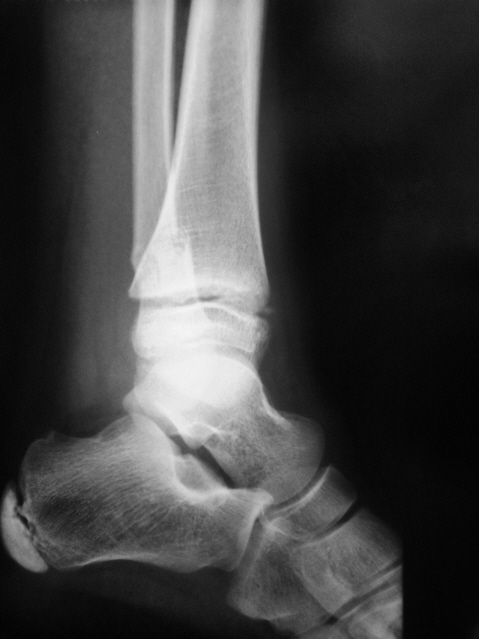

Направлен пациент хирургом для рентгенографии голеностопного сустава.

Что посоветуете уважаемые коллеги?

Согласен с Вами, коллега, без эндопротезирования здесь не обойтись.

Эээ... Простите. Без эндопротезирования голеностопного сустава? По поводу последнего случая?

По всей видимости, это по поводу тазобедренных суставов.